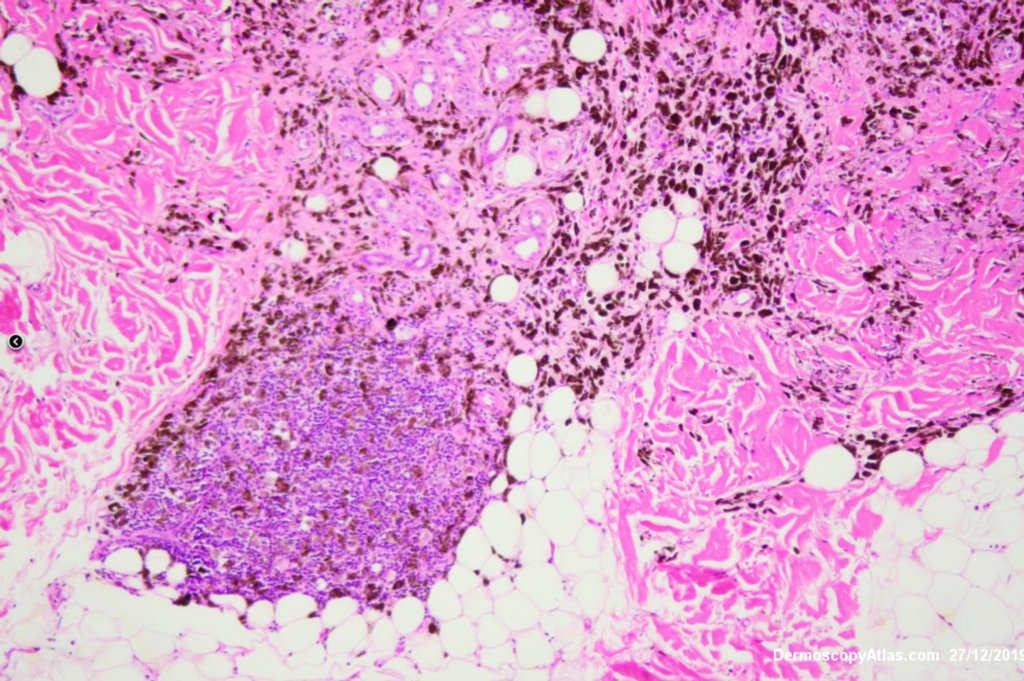

Diagnosis: Melanoma metastases

This elderly man had a preceeding lentigo maligna but subsequently developed in transit metastases as shown by the blue macules and papules on his cheek. He was treated with Keytruda. PET scan was negative for spread elsewhere.

It is important to treat lentigo maligna early to stop a situation like this from developing.